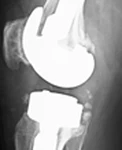

Hikaye: Dört yıl önce sağ dize total protezi uygulanan hastanın üç ay önce ortopedi kliniğine aynı dizde ağrı ve eklemde kısıtlılık ile başvurduğu ve mevcut protezin revize edilmesi kararı verildiği öğrenildi. Başvurmasından iki ay önce revizyon diz protezi yapılıyor. Ameliyattan sonra düşük ayak gelişiyor. Ev egzersizleri, ortez ve multivitamin ile taburcu ediliyor.